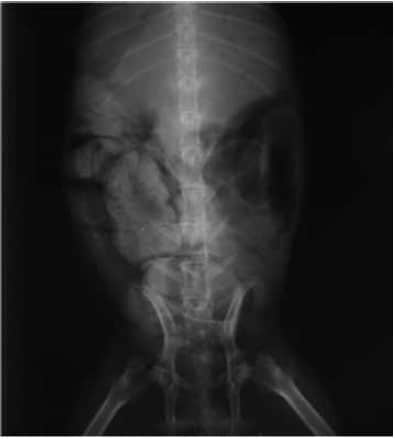

体温:36.7℃、呼吸:70次/min、心跳:150次/minX光片检查:

图二:正位片(肠道内有大量粪便及胃内有大量食糜及气体)